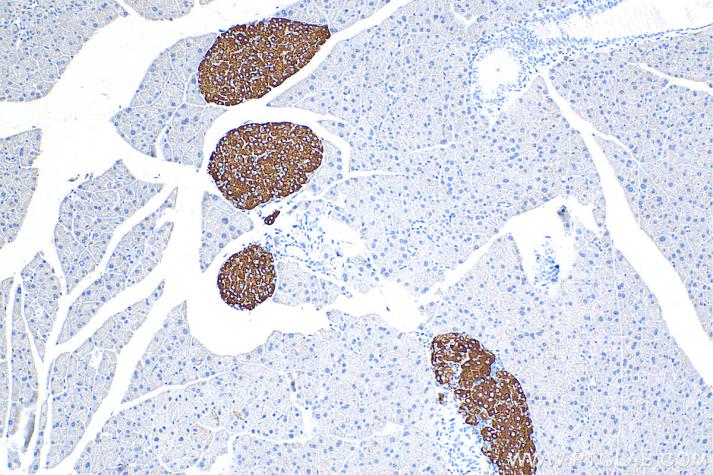

IHC analysis of mouse pancreas tissue with Proteintech’s Synaptophysin rabbit polyclonal antibody (17785-1-AP). Heat-induced epitope retrieval was performed using Tris-EDTA Antigen Retrieval Buffer (PR30002).